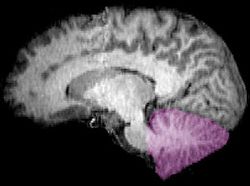

cerebellum (Latin for "little brain") is a major feature of the hindbrain of all vertebrates. Although usually smaller than the cerebrum, in some animals such as the mormyrid fishes it may be as large as or even larger.[1] In humans, the cerebellum plays an important role in motor control. It may also be involved in some cognitive functions such as attention and language as well as emotional control such as regulating fear and pleasure responses,[2][3] but its movement-related functions are the most solidly established. The human cerebellum does not initiate movement, but contributes to coordination, precision, and accurate timing: it receives input from sensory systems of the spinal cord and from other parts of the brain, and integrates these inputs to fine-tune motor activity.[4] Cerebellar damage produces disorders in fine movement, equilibrium, posture, and motor learning in humans.[4]

Anatomically, the human cerebellum has the appearance of a separate structure attached to the bottom of the brain, tucked underneath the cerebral hemispheres. Its cortical surface is covered with finely spaced parallel grooves, in striking contrast to the broad irregular convolutions of the cerebral cortex. These parallel grooves conceal the fact that the cerebellar cortex is actually a continuous thin layer of tissue tightly folded in the style of an accordion. Within this thin layer are several types of neurons with a highly regular arrangement, the most important being Purkinje cells and granule cells. This complex neural organization gives rise to a massive signal-processing capability, but almost all of the output from the cerebellar cortex passes through a set of small deep nuclei lying in the white matter interior of the cerebellum.[5]

The cerebellum is located in the posterior cranial fossa. The fourth ventricle, pons and medulla are in front of the cerebellum.[8]